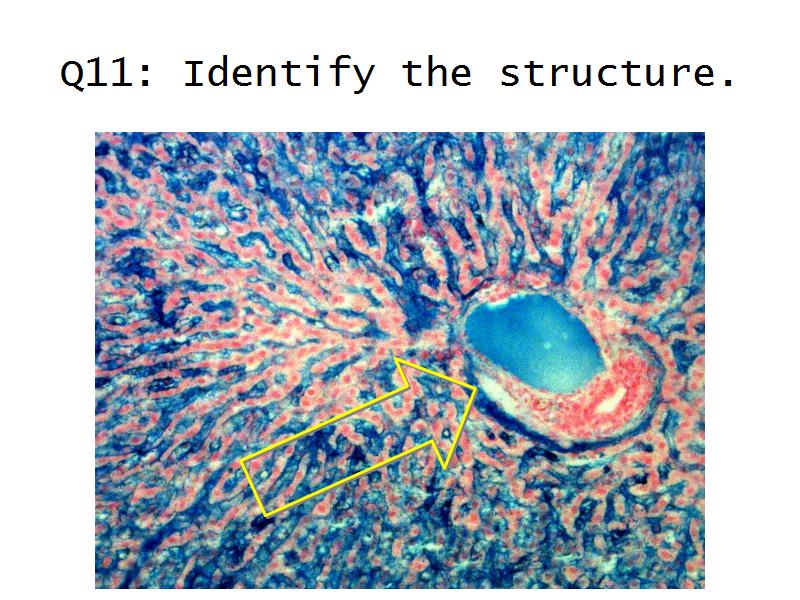

Kidney

Slides 28 & 76

Kidney: Objectives

- Basic arrangement of nephrons and collecting tubules in the kidney

- Structure of the nephron and collecting tubules

- The renal corpuscle

- Make an annotated diagram of a nephron, including the juxtaglomerular apparatus. Indicate the flow of blood and water in each part, and how solutes are filtered, secreted and reabsorbed.